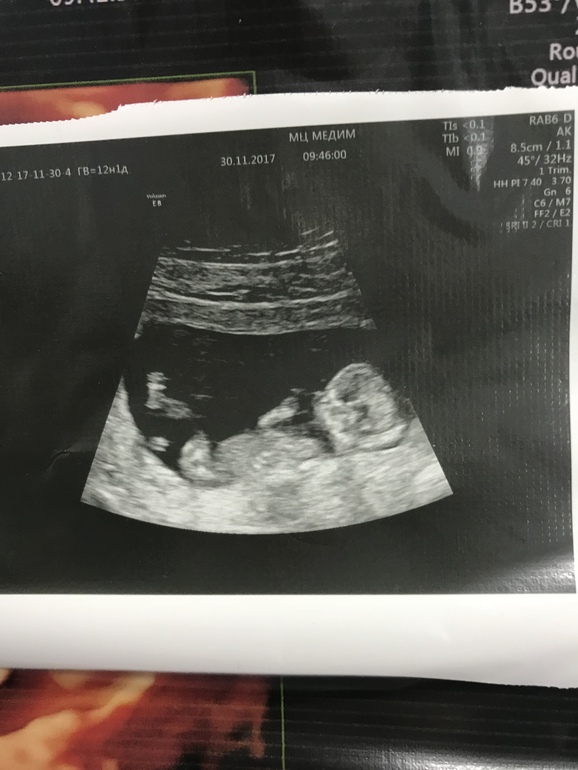

1 скрининг в платной)

Не удержалась я и пошла сегодня на скрининговое УЗИ в платный центр. Параметры носовой кости и твп немного отличаются, но не знавчитеоьно. Показали мне все органы, все у нас развито правильно к данному сроку) малышка спала, поэтому получилось посмотреть все очень

внимательно) вчера предположили мальчика, а сегодня девочку ) половой орган мне показали //, а у мальчиков / такой, говорит) но не на 100%, конечно))) я счастлива )

Хотела написать про плаценту, но от радости забыла) плацента в краевом предлежании, а не полном. Зев не перекрывает, шейка плотно закрыта. Сказали, что она поднимется ещё, и сейчас какие-то диагнозы ставить неверно)